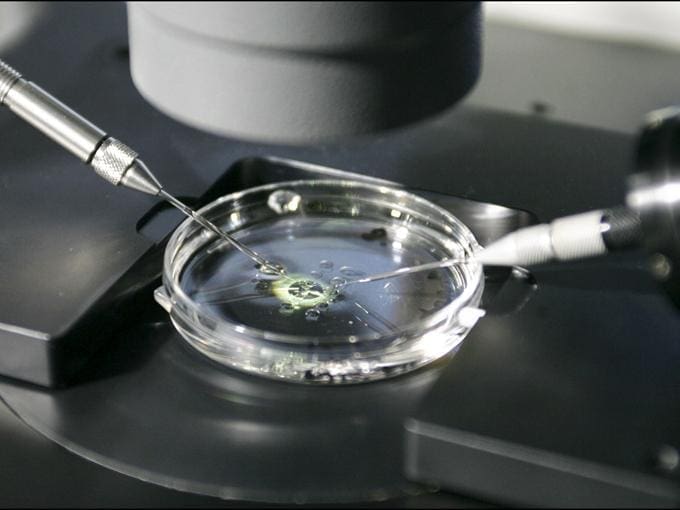

¿Por qué elegir una clínica especializada en alta complejidad reproductiva?

La búsqueda de un embarazo puede llegar a ser un proyecto largo y lleno de incertidumbre, sobre todo cuando el resultado no llega en el momento esperado. Muchas mujeres y […]